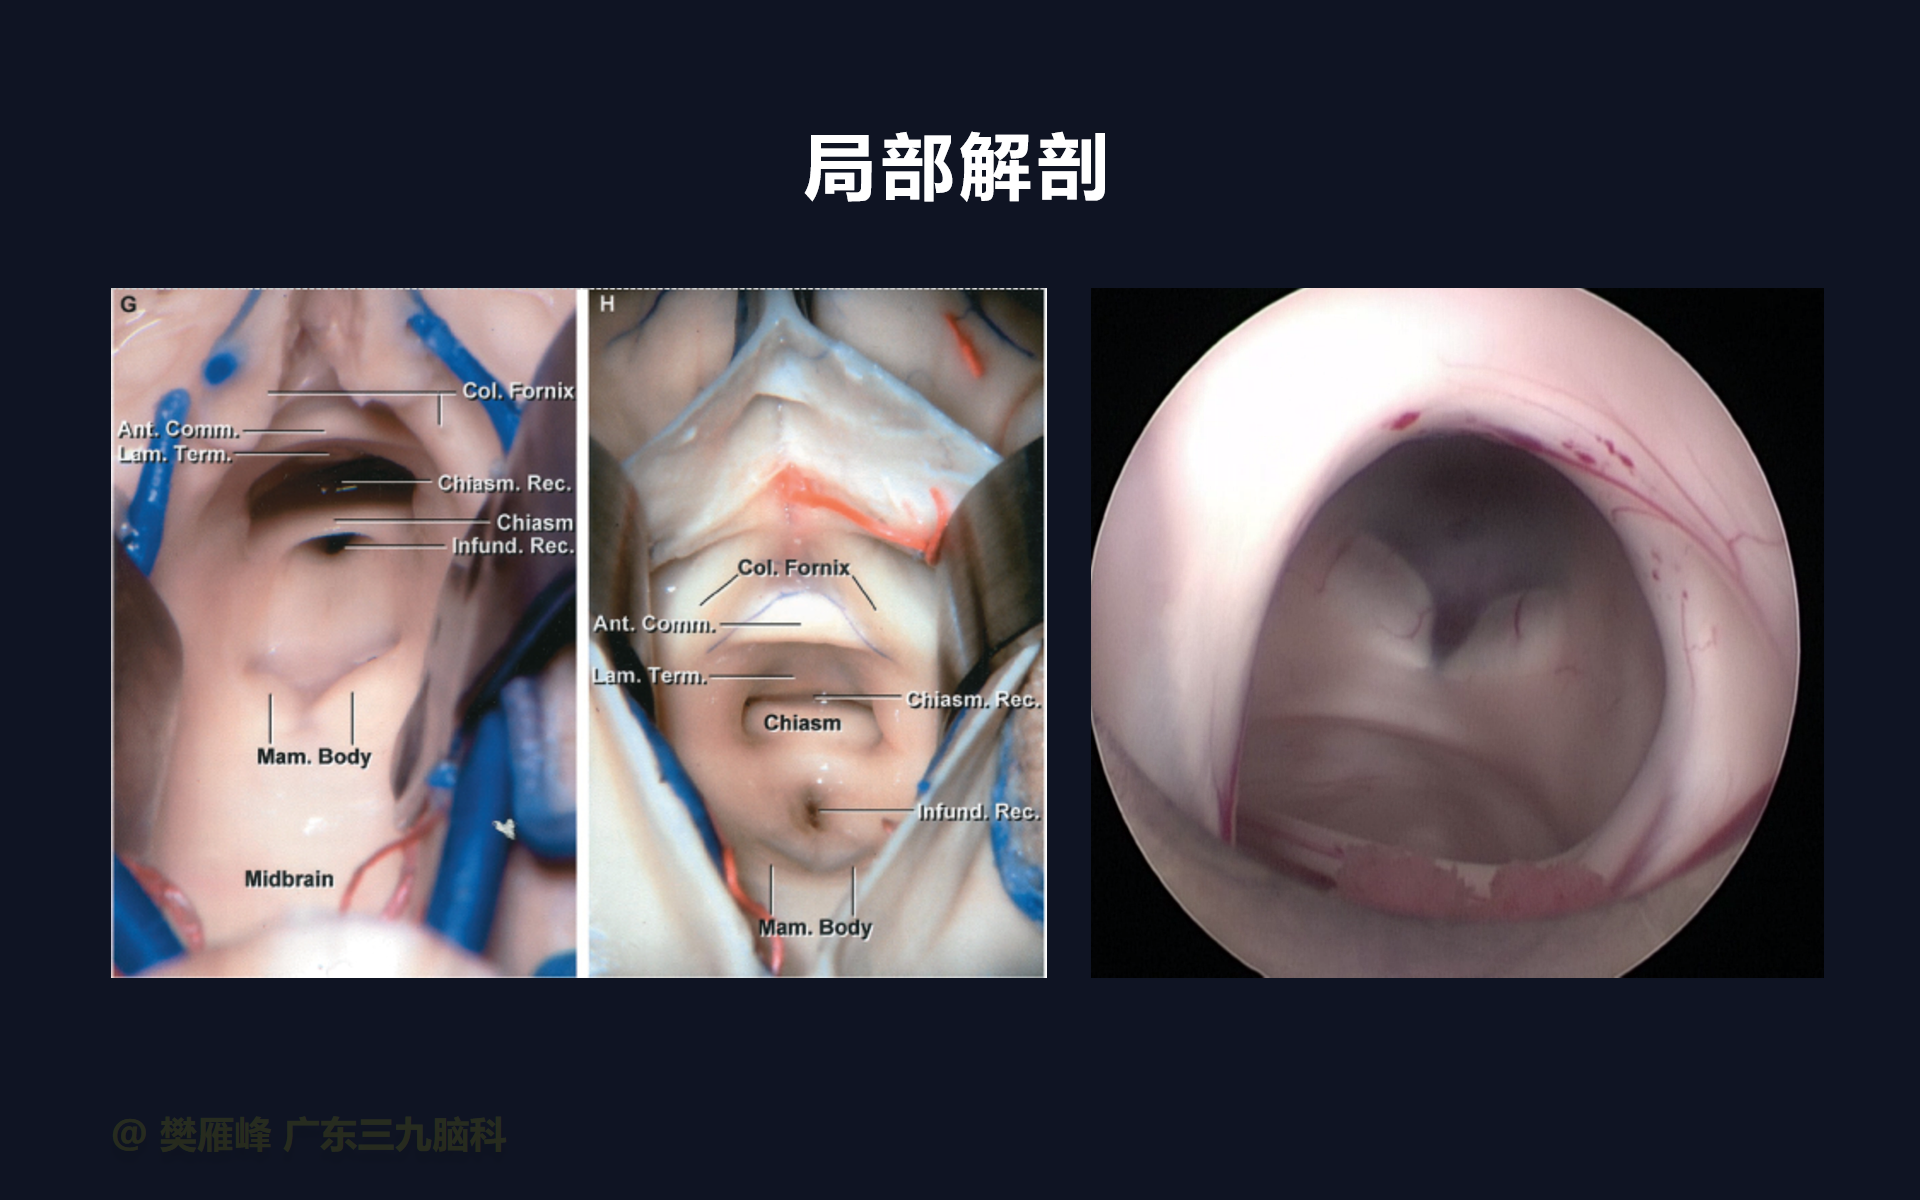

第三脑室底造瘘时可同时行内镜下活检,这样,一次手术可处理脑积水获得病理诊断。

第三脑室后部肿瘤切除术前行ETV不仅有利于控制急性HCP,而且可以防止术后继发HCP的发生和最大限度地减少术后早期并发症。

在这个二维手术视频中,展示了2例神经内镜下三脑室底造瘘+活检治疗三脑室后部肿瘤的方法。患者均为三脑室后部病变导致的梗阻性脑积水,病理结果1例为生殖细胞瘤,1例为淋巴瘤,在经过术后的放化疗病情均得到控制,生活质量满意。我们展示了安全的病变活检和第三脑室造瘘的技术要点,以最大限度减少术后继发脑积水和早期并发症。